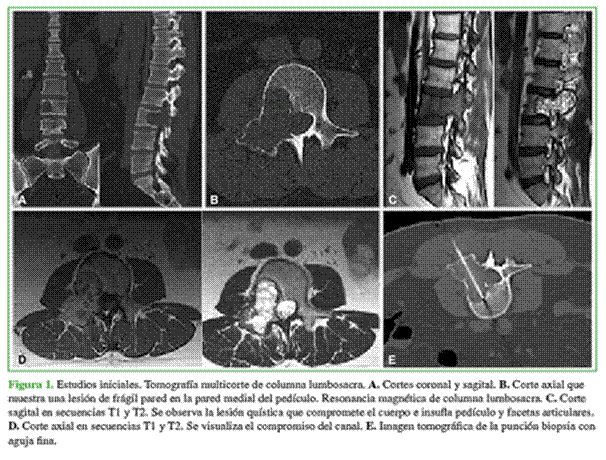

Mujer de 38 años que acudió a la consulta con dolor lumbocrural a predominio derecho que fue aumentando con el tiempo, no tenía déficit motor, las caderas estaban libres, la maniobra de Lasegue fue negativa, la de Wasserman, positiva a predominio derecho. Se detectó hiporreflexia rotuliana bilateral con hiperestesia superficial y profunda de L3 y L4 derecho, pie cavo varo y pulsos positivos bilaterales. Refirió litiasis biliar. Concurrió con un centellograma óseo corporal total y una tomografía computarizada por emisión de fotón único (SPECT) con 20/30 mCi de TC99 que informaban una lesión única en L3; una tomografía previa de tórax, abdomen y pelvis no revelaba hallazgos de metástasis o algún otro foco tumoral posible, antes de la punción para determinar el tipo y la estirpe de la patología en cuestión; y una mamografía BI-RADS 2 que no mostraba enfermedad tumoral.

Se solicitaron otros estudios por imágenes, tomografía helicoidal y resonancia magnética, y se confirmó la ubicación de la lesión dentro de la vértebra. La biopsia por punción guiada por tomografía (Figura 1) confirmó el diagnóstico de QOA. A los dos meses de la consulta y los estudios, el quiste tuvo una evolución tórpida y los síntomas se incrementaron; por lo tanto, se solicitaron nuevos estudios en los que se observó la progresión e inclusive una fractura patológica en el cuerpo de L3 (Figura 2).